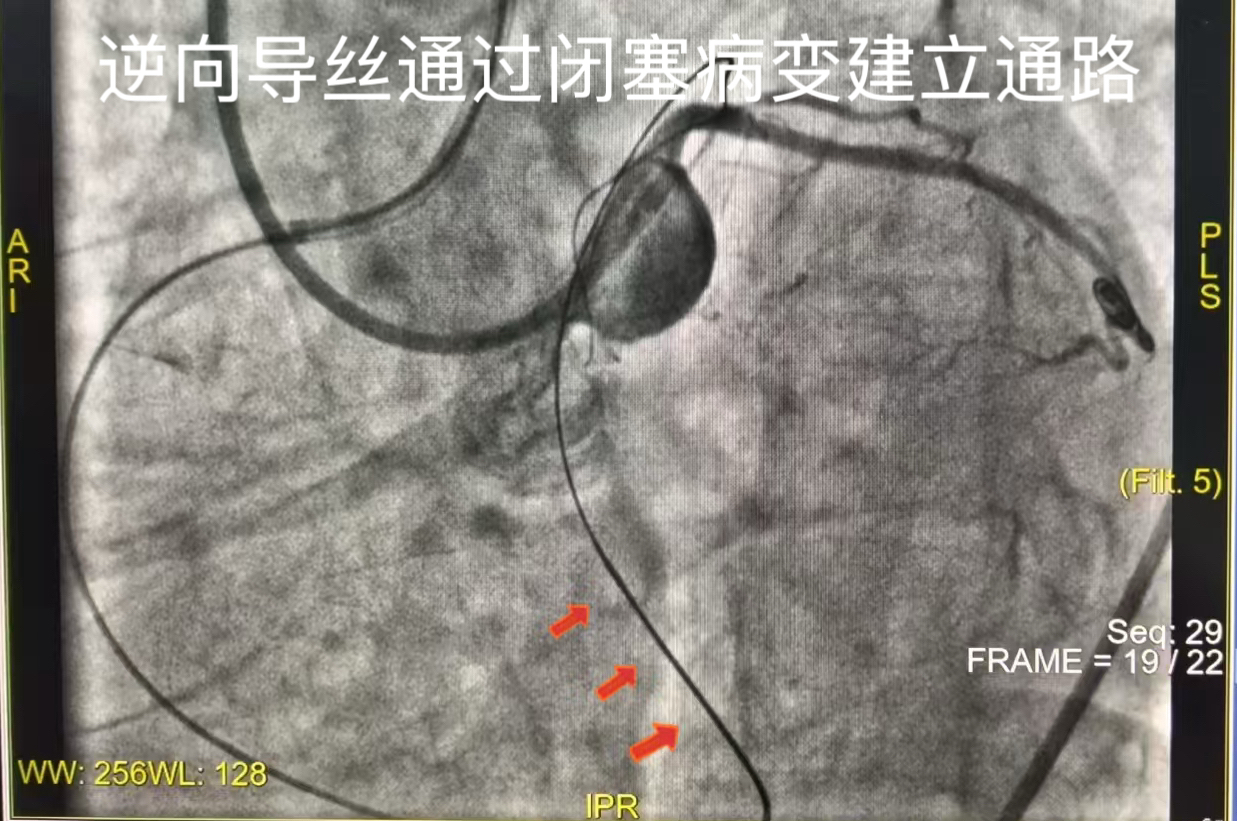

丛占春主任带领团队尝试经LAD正向开通闭塞血管,但因病变处解剖结构复杂,导丝多次尝试均无法通过病变段。面对困境,团队决定采用逆向术式开通LAD,选取RCA向LAD发出的侧支循环作为逆向入路,将导丝、微导管精准送至LAD闭塞病变远端。

通过逆向造影,清晰显示了闭塞段的长度、形态及钙化程度,借助逆向导丝成功建立血管通道,逐步扩张前降支(LAD)闭塞段。通过血管内超声检查,进一步显示了病变性质与血管情况,选择药物球囊对病变处进行充分扩张,实现了LAD血管的成功再通,恢复了心肌正常供血,同时于LM-LCX植入一枚支架,解决其重度狭窄问题。